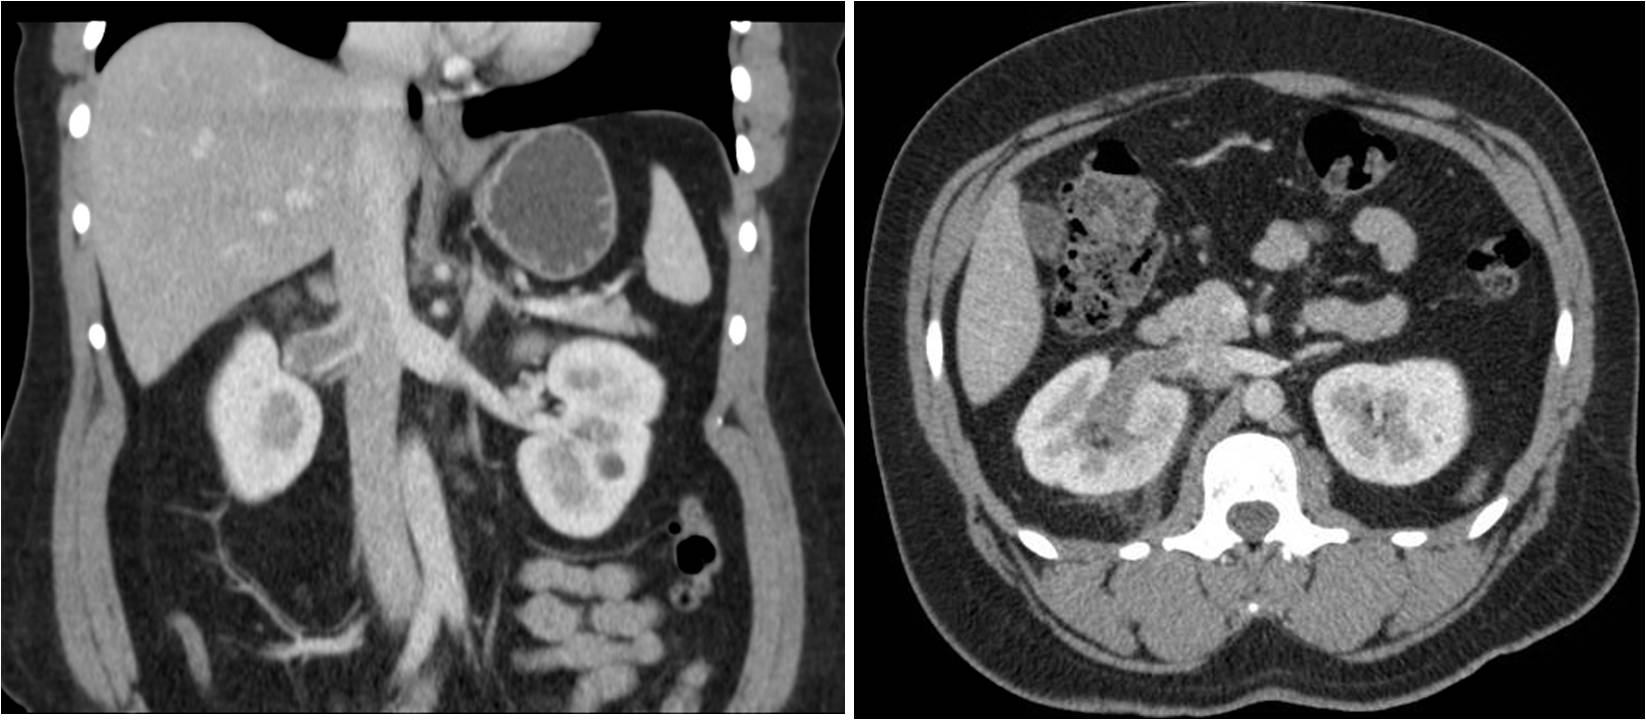

Renal vein thrombosis should be suspected in patients with flank pain and hematuria, especially if accompanied by impaired renal function. The best imaging studies to make the diagnosis are computed tomography (as seen above) or magnetic resonance imaging. On imaging a filling defect will be seen within the renal vein. The filling defect may extend into the inferior vena cava. The kidney itself may show a renal cell carcinoma or edema from congestion. Theoretically renal duplex ultrasound will show lack of flow within the renal vein, however this is not a reliable test for this diagnosis. If you cannot identify normal flow, but you still suspect the diagnosis, you should opt for another imaging modality.